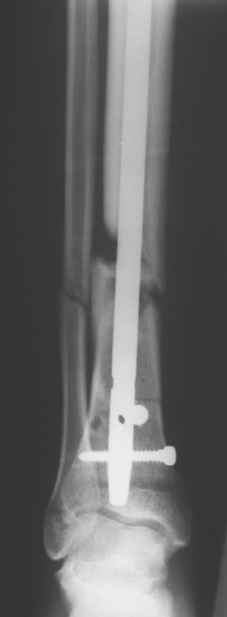

Re: Свободные осколки и штифтование

послал Юрий Алексеевич Булахтин 02 Апрель 2009, 14:46

Сегодня прооперировали без открывания. Хотел-бы услышать комментарии по поводу послеоперационной нагрузки.